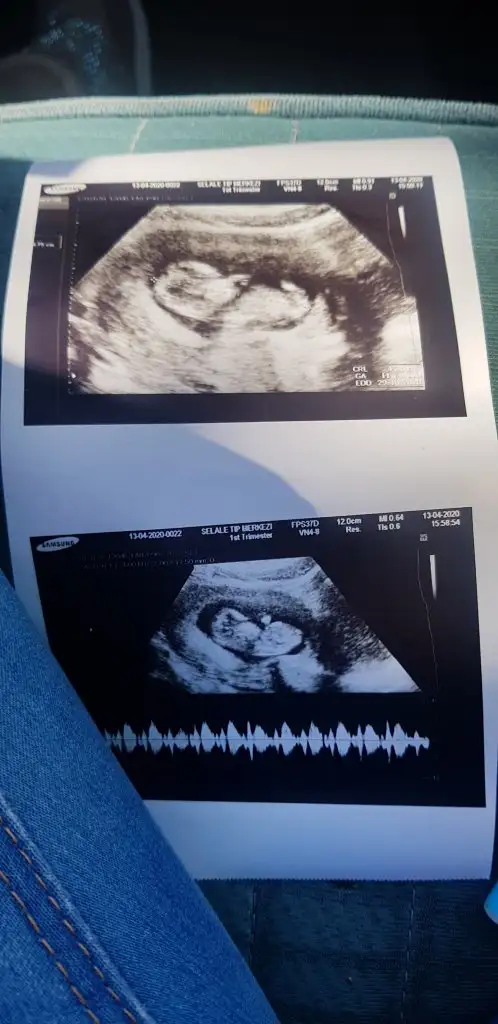

Kaç haftalık 11 12 13 hafta olmalı nublar kapalı kafa yapısı erkek gibi tutmayabilir nub için istediğim haftalarıda paylaşınBenimde bebeğime bakarmısınız dr ters olduğu için göremedi Eki Görüntüle 2619582 Eki Görüntüle 2619582 Eki Görüntüle 2619583

13+2 haftalıkKaç haftalık 11 12 13 hafta olmalı nublar kapalı kafa yapısı erkek gibi tutmayabilir nub için istediğim haftalarıda paylaşın![]()

Nub için 11 12 13 hafta olmalı sanki kız ama emin değilim istediğim usg leri paylaşınMerhaba bana da yorum yapabilir misiniz